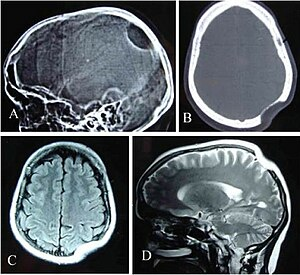

Radyolojik bulgular kemiklerde oluşan lezyonun evresine göre değişmektedir

Kemik grafilerinde subkortikal ve intermedullar yama tarzında radyolusent ostelitik lezyonlar tespit edilir. Bu amaçla direkt grafi, MR ve BT kullanılır

Osteolitik lezyonlar baş, klavikula, vertebrada, kostalarda, pelviste ve alt ekstremitede görülebilmektedir